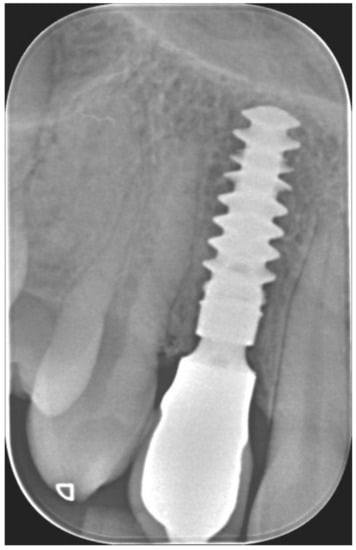

Figure 4.

Immediate temporization of immediately placed implant.

Figure 5.

Periapical X-ray at immediate temporization.